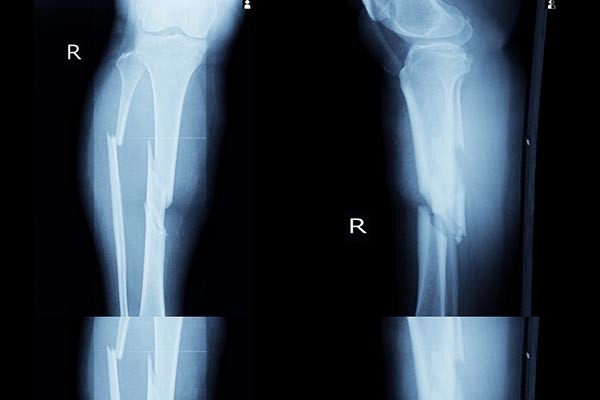

csonttores

A csonttörés felismerésében a számítógép és az orvosok egyforma hatékonysággal dolgoztak